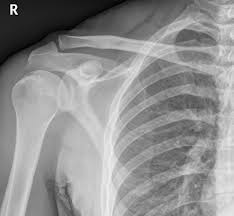

Receive precise and affordable imaging with our X-Ray Left Shoulder AP (anteroposterior) and Lateral views. These scans provide detailed front and side images of the left shoulder joint, helping detect fractures, dislocations, arthritis, and other abnormalities. Our NABL and NABH-accredited diagnostic centers ensure reliable results to support accurate diagnosis and effective treatment.

Experience comprehensive and precise diagnostic imaging with the X-Ray Left Shoulder AP (anteroposterior) and Lateral views at Medifyhome. This advanced imaging procedure provides detailed front and side views of your left shoulder joint, enabling healthcare professionals to thoroughly examine the bones, joint spaces, and surrounding soft tissues.

The shoulder is a complex joint prone to various conditions including fractures, dislocations, arthritis, rotator cuff injuries, and other soft tissue disorders. The AP view offers a clear look at the shoulder’s overall structure, while the lateral view provides additional perspectives critical for accurate diagnosis.